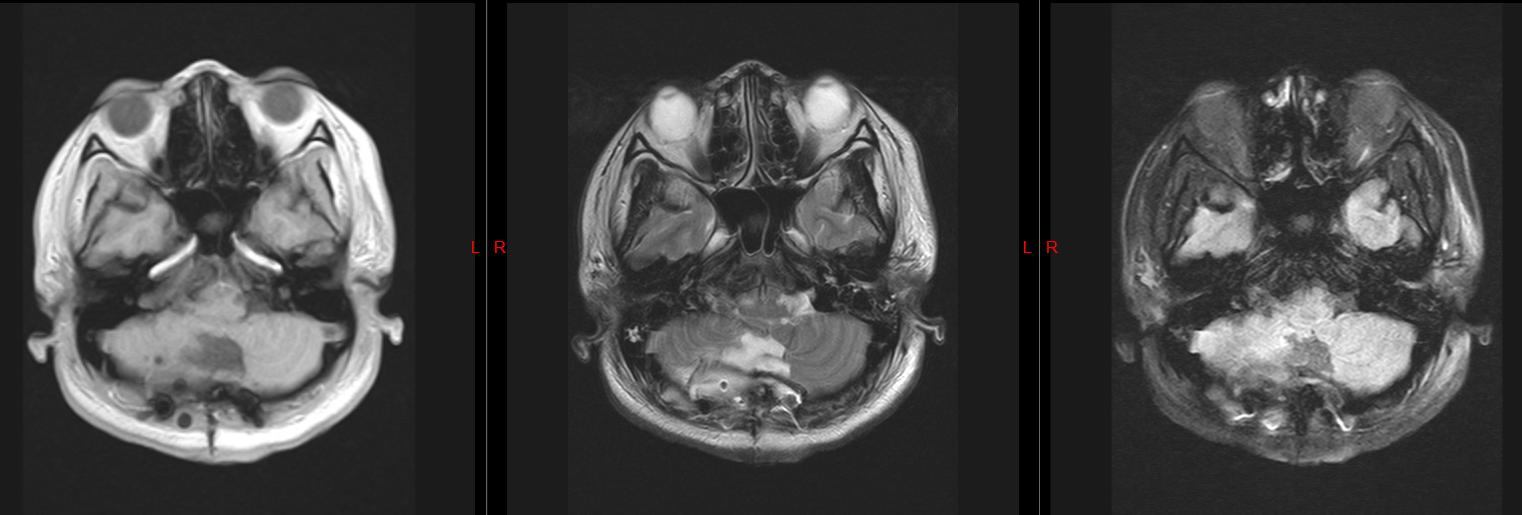

头颅磁共振检查结果显示

我的小脑上长了一个 肿瘤

压迫脑干

并且还有 脑积水

术后复查头颅磁共振

肿瘤完整切除